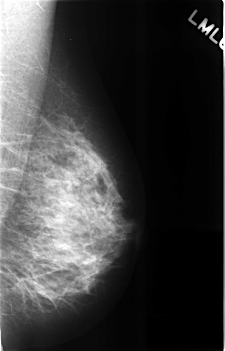

C_0308_1.LEFT_MLO

LEFT_MLO LINES 4552 PIXELS_PER_LINE 2920 BITS_PER_PIXEL 12 RESOLUTION 50 NON_OVERLAY